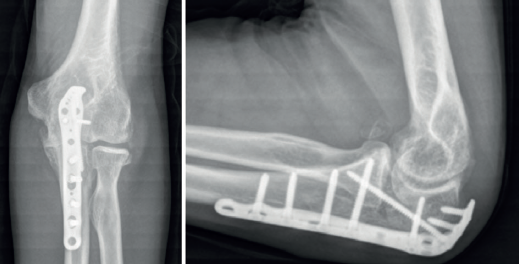

retla.07214.fs2409015-figura9.png

Figura 9. Imágenes radiológicas tras la reintervención en la que se retiró todo el material de osteosíntesis a través de un abordaje posterior del codo que permitió reducir y fijar el cúbito con una placa específica del olécranon y tornillos adicionales, la fractura de la coronoides con un tornillo de la placa, desde posterior a anterior, y la colocación de una prótesis de la cabeza del radio. Al finalizar la intervención se comprobó la reducción y la estabilidad de la articulación radiocubital proximal, pero el codo se subluxaba al colocar el antebrazo en supinación y flexión de 30°, por lo que durante las primeras 6 semanas se permitió la flexión libre del codo con el antebrazo en rotación neutra y se limitó la extensión a -30°.